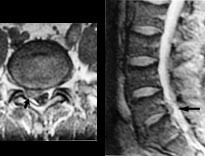

MR gir verdifull informasjon hos pasienter med degenerative lidelser i columna. En av de store fordelene ved MR er at bein og bløtdeler kan demonstreres i samme bilde, men atskilles pga. forskjellige signaler. Foreløpig kan det være et problem at oppløsningen i bildene ikke er så god som i konvensjonelle røntgenbilder. Enkelte detaljer kan derfor fremstilles bedre ved konvensjonelle radiologiske metoder, f.eks. rotskjeder ved myelografi. Prolaps kan som oftest fremstilles tilfredsstillende med CT (19), men i de fleste tilfeller er MR-bildene lettere å tolke (fig 6) (5).

Symptomgivende metastaser til columna opptrer imidlertid i ca. 5 % hos pasienter med maligne svulster. MR er svært følsom for metastaser (20) og det er viktig å huske at normalt utseende konvensjonelle røntgenbilder ikke kan utelukke selv uttalte destruktive skjelettforandringer (fig 7).